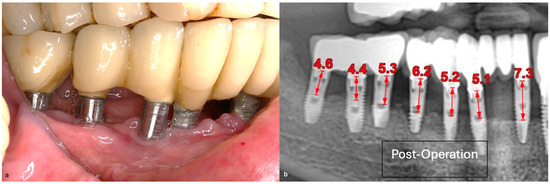

A generally healthy 63-year-old female presented to our clinic with chief complaints of foul odor and occasional pain emanating from dental implants located in the mandibular right quadrant (from implants #42 to #47). Clinical examination revealed peri-implantitis, with a high level of BoP and suppuration around the affected implants. The radiographic evaluation confirmed moderate-to-severe vertical bone loss, consistent with a diagnosis of peri-implantitis (Figure 19).

In this case, after achieving the renewed implant surface (machined), the regenerative procedure involving bone grafting and collagen membrane was not performed. The flaps were repositioned and secured with tension-free primary closure. The postoperative instructions included chlorhexidine 0.12% (Taro Pharmaceuticals, Haifa Bay, Israel) rinses and systemic antibiotic coverage for 5 days. Regular clinical and radiographic evaluations were conducted at 1 month, 3 months, 6 months, and 12 months, postoperatively. At the six-month follow-up, the clinical examination revealed significant improvements, with resolution of inflammation and no BoP; the patient reported a complete resolution of the initial chief complaints. Radiographs demonstrated stabilization and initial signs of bone regeneration around treated implants. At the 12-month follow-up, the bone level and PDs were stabilized (Figure 23), and the implant surface adequately accommodated the gingival tissue (Figure 24).

Figure 19. (a) Initial clinical assessment; (b) Periapical X-ray presenting the measurements (red arrows) from the platform to the bone; (c) The panoramic view shows the vertical bone loss found at baseline.

Figure 23. Radiographic bone level and probing depth comparing the baseline and 12-month results.

Figure 24. (a) Clinical follow-up after 12 months; (b) Radiographic outcome after 12 months.